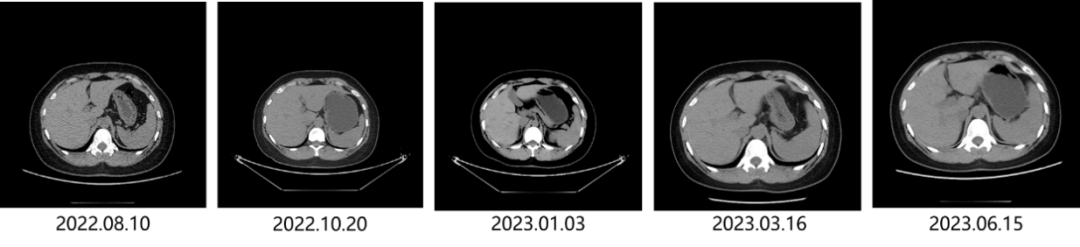

• 2022.04.15 完善PET/CT检查,提示:乳腺、肝脏、骨转移好转,颅脑左额叶、枕叶新发两个等密度结节。2022.04.21 完善颅脑MRI检查,提示:左额叶、枕叶多发结节,大者约1.8cm*1.4cm。

• 2022.04.29开始行T-DM1方案治疗。定期复查,肝脏病灶持续缩小;颅内转移灶略缩小,控制稳定;骨转移灶控制稳定。治疗过程中发生≤2级血小板减少,对症给予海曲泊帕升血小板治疗,后血小板恢复正常。

• 2023.06.15 患者颅内病灶稳定,肝脏转移灶消失,骨转移灶稳定。

图2 T-DM1治疗颅内转移灶变化